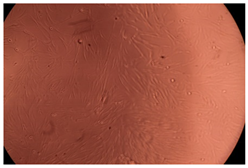

The results of the cytotoxicity assay, given in Figure 5, indicate that the tested PMs at all three established concentrations (10, 50, and 100 µg/mL) did not show cytotoxic effects on fibroblast cells at either 24 or 48 h after incubation. The percentages of cell viability were high, over 90%, in cells that were exposed to a concentration of 10 µg/mL for 24 h for all tested materials. Even at 48 h after incubation, the percentage of cell viability was as high as 90.4% in cells exposed to a concentration of 10 µg/mL for the Cop B sample. For both drug-loaded PMs, the cell viability decreased slightly at all tested concentrations. It also appears that the Dorzolamide-loaded PMs have slightly lower cell viability as compared to IMC-loaded PMs. Micrographs of the fibroblast cells after incubation times of 24 and 48 h are provided in Table 2.

Table 2.

Micrographs of fibroblast cells after 24 and 48 h incubation times, respectively.

As the cell viability values are all over 80%, the results indicate that the PMs, at the established concentrations, can be used successfully for in vivo biomedical applications.